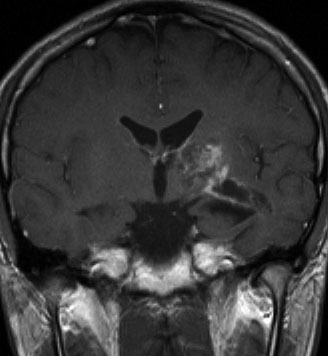

尿崩症にて発症した2年後にようやく小さなneurohypophyseal germinomaを発見された9歳女児例です。術前のT1強調画像では下垂体後葉のbrightnessが消失し,下垂体柄が腫大しています(左側)。ガドリニウムで腫瘍部分が増強されますが前葉よりは低信号となっています(右側)。経蝶形骨洞生検術で確定診断を得た後に,シスプラチンとエトポシドを1コース投与したところ腫瘍は完全消失しました。3コース後に24Gy12分割の放射線治療を加え再発はありません。残っていた下垂体前葉機能は治療後に少し改善しました。生検術では,トルコ鞍底を開けて下垂体後葉の下部を目標にして小さな組織採取をします。GHDがあっても前葉にはmassとしての腫瘍が無いと考えた方がいいでしょう。

この例は18歳,HCG 0.1mIU/ml,尿崩症で発症しました。神経下垂体ジャーミノーマなので,下垂体前葉のみが残って後葉から視床下部が腫瘍化しています。よくよく見ると松果体にもごく小さな腫瘍があります。右のCISS画像で松果体の腫瘍化が明瞭です。

経鼻生検術で下垂体後葉部分がgerminomaということを確認してからICE (IFO/CDDP/VP-16)を1コース加えて3週間後の画像です。腫瘍は灰白隆起の部分を残してほぼ消失しています。松果体部の腫瘍も消えています。典型的なgerminomaの化学療法反応性を示しています。下垂体前葉機能は正常,尿崩症も少し良くなりました。